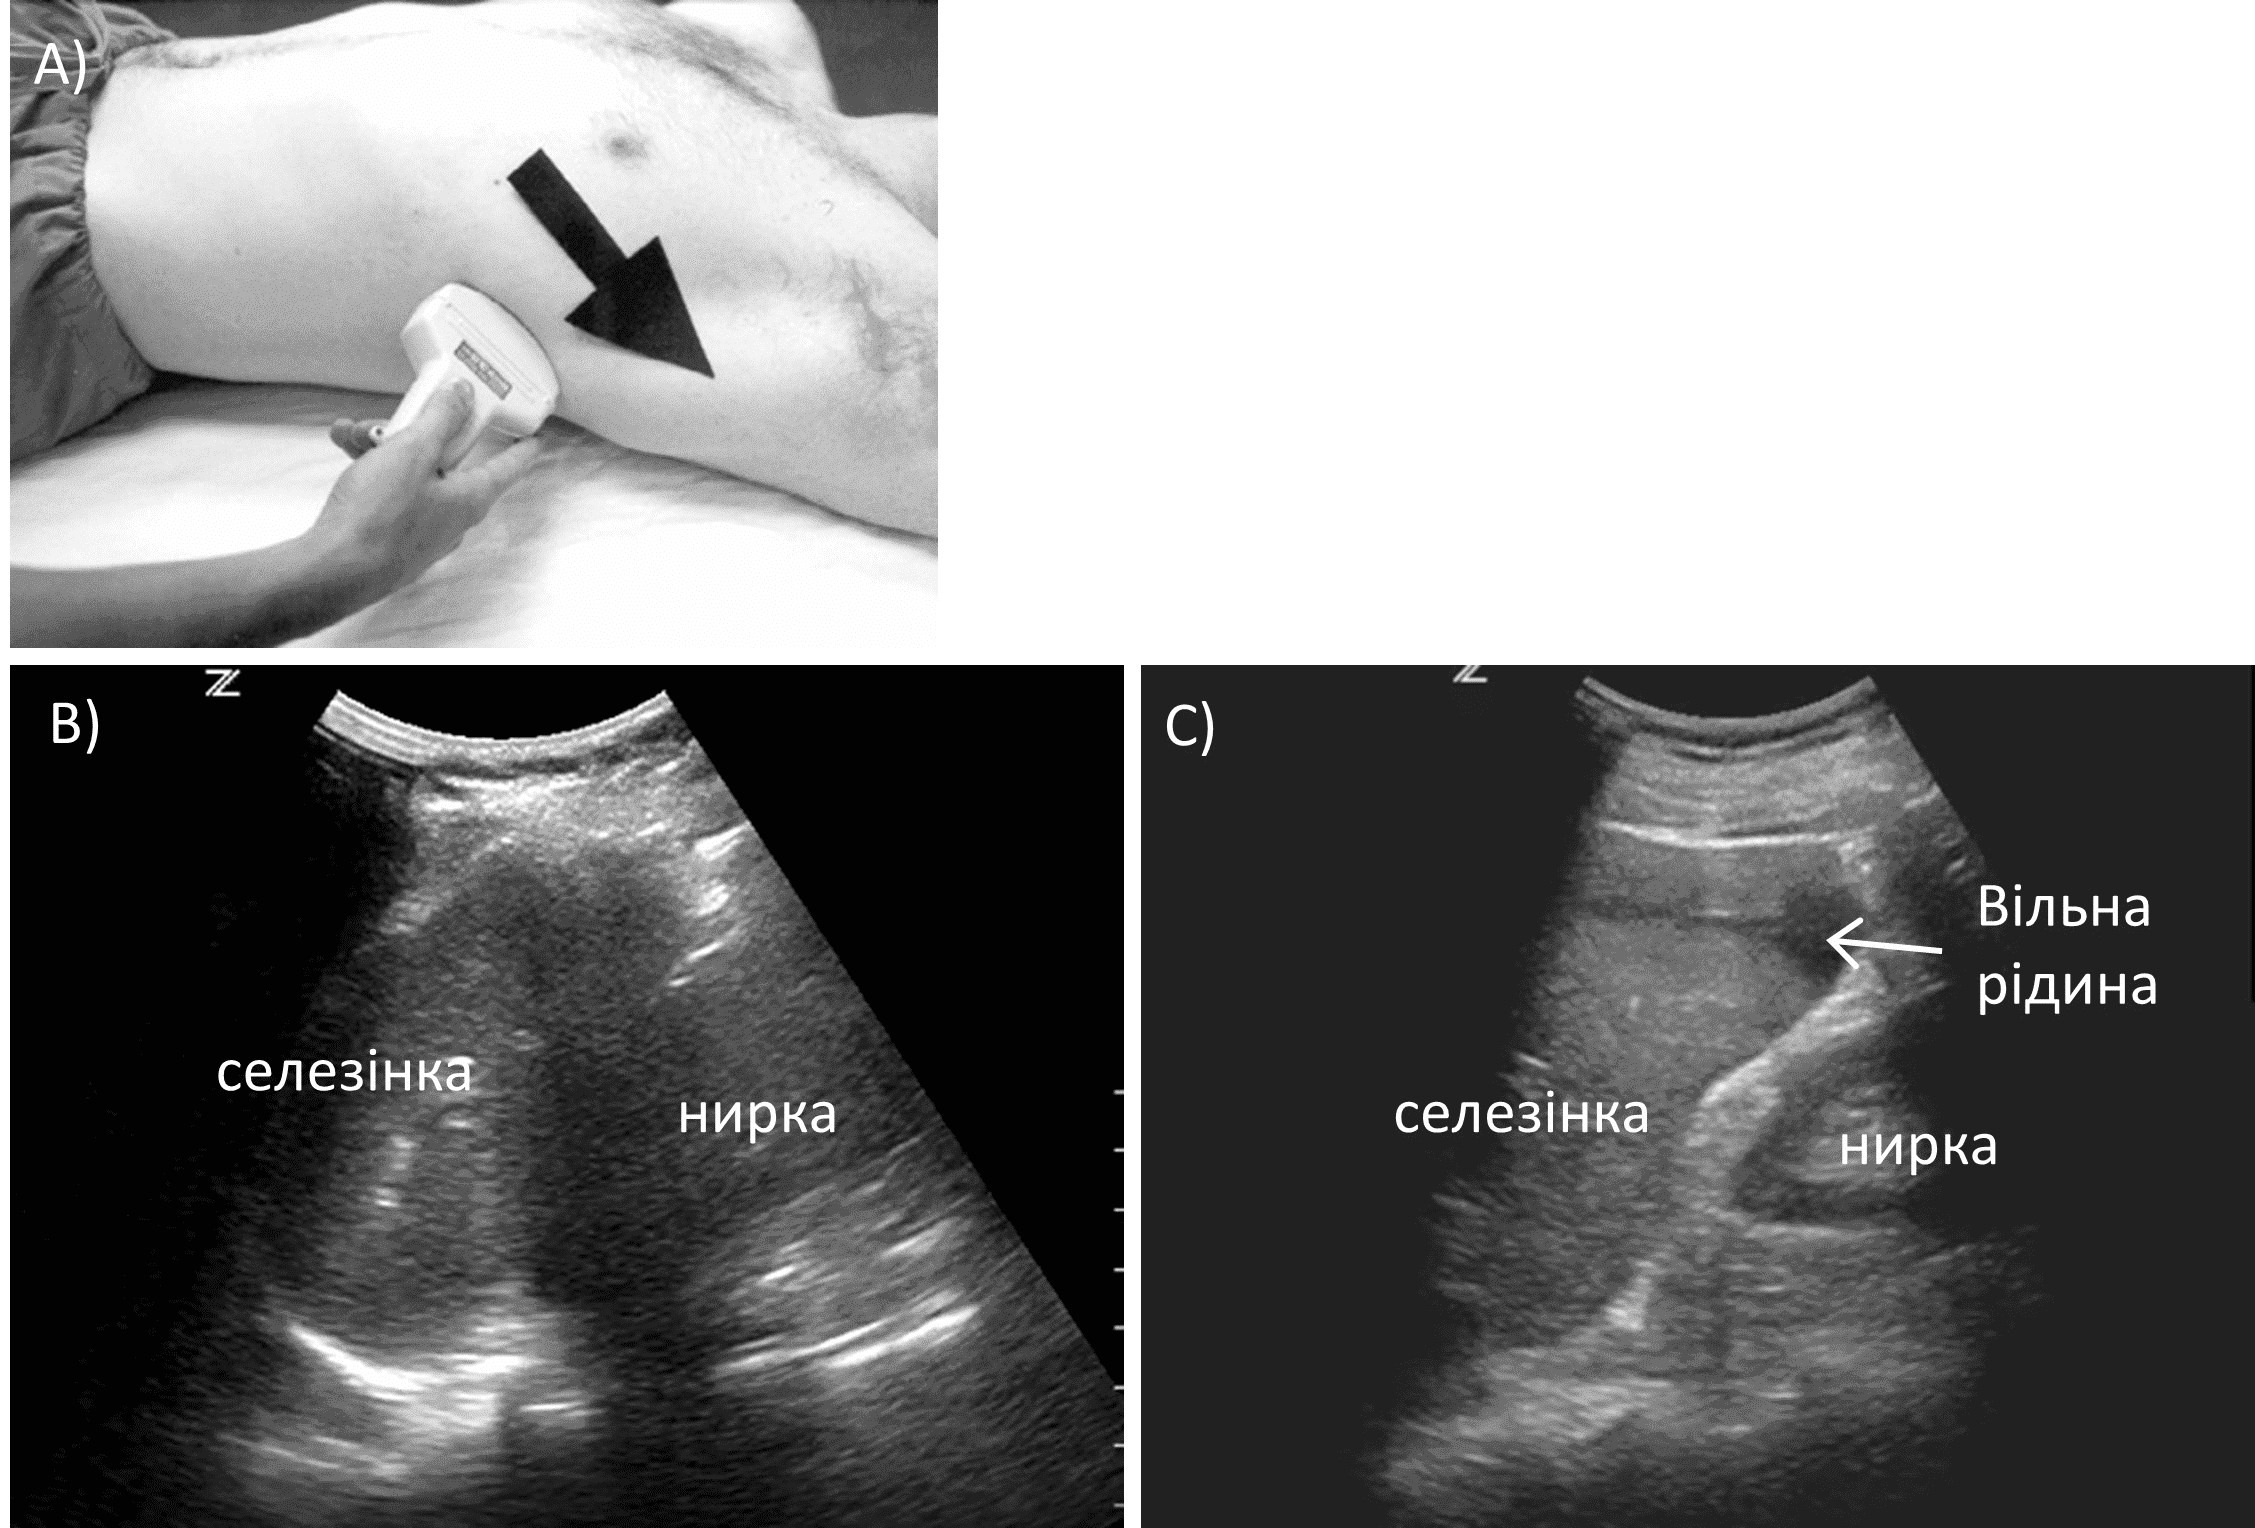

Ця проекція використовується для візуалізації селезінково-ниркового заглиблення. Зліва селезінка розташована більш до заду та вище, ніж печінка справа. Таким чином, лівий бік візуалізують, розташувавши зонд позаду на задній пахвовій лінії, як правило, у 8-му або 9-му реберному просторі, маркер спрямований у бік голови пацієнта. Зонд знову рухають віялоподібно вперед і назад (зобр. 6).

Зобр. 6. Проекція лівого фланку.

A) Позиціонування датчика. B) Норма. C) Вільна рідина.

Важливо одночасно візуалізувати селезінку та нирку, щоб не пропустити скупчення рідини. Тінь ребер також може заважати візуалізації у цій проекції, цьому можна запобігти так само як і з правого боку, однак  слід зауважити, що датчик слід повертати за годинниковою стрілкою, щоб він лежав паралельно ребрам. Слід також оцінити ділянку позаду та вище від селезінки, під діафрагмою. Дослідження цієї області може підвищити чутливість цього тесту, оскільки кров спочатку може накопичуватися в цій області залежно від анатомічних особливостей пацієнта.